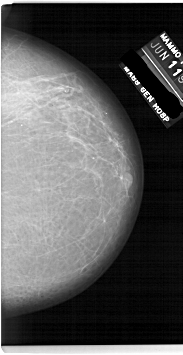

A_1920_1.RIGHT_CC

RIGHT_CC LINES 6736 PIXELS_PER_LINE 3466 BITS_PER_PIXEL 12 RESOLUTION 43.5 NON_OVERLAY